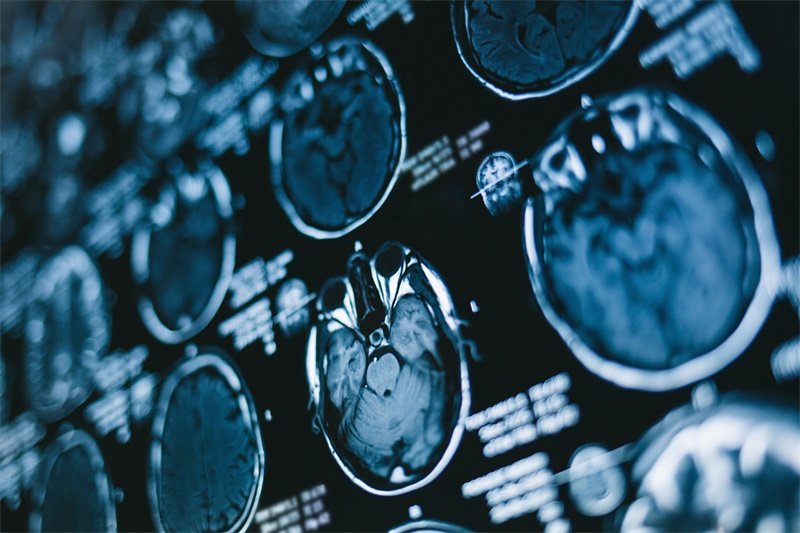

影像学检查

影像学检查是最常用的诊断工具,包括CT扫描和MRI。这些技术能够清晰显现出脑部内部结构,帮助医生判断占位的大小、形态以及位置。

与此同时,根据影像结果,医生可以进一步规定是否需要进行活检,以确认肿瘤的性质。